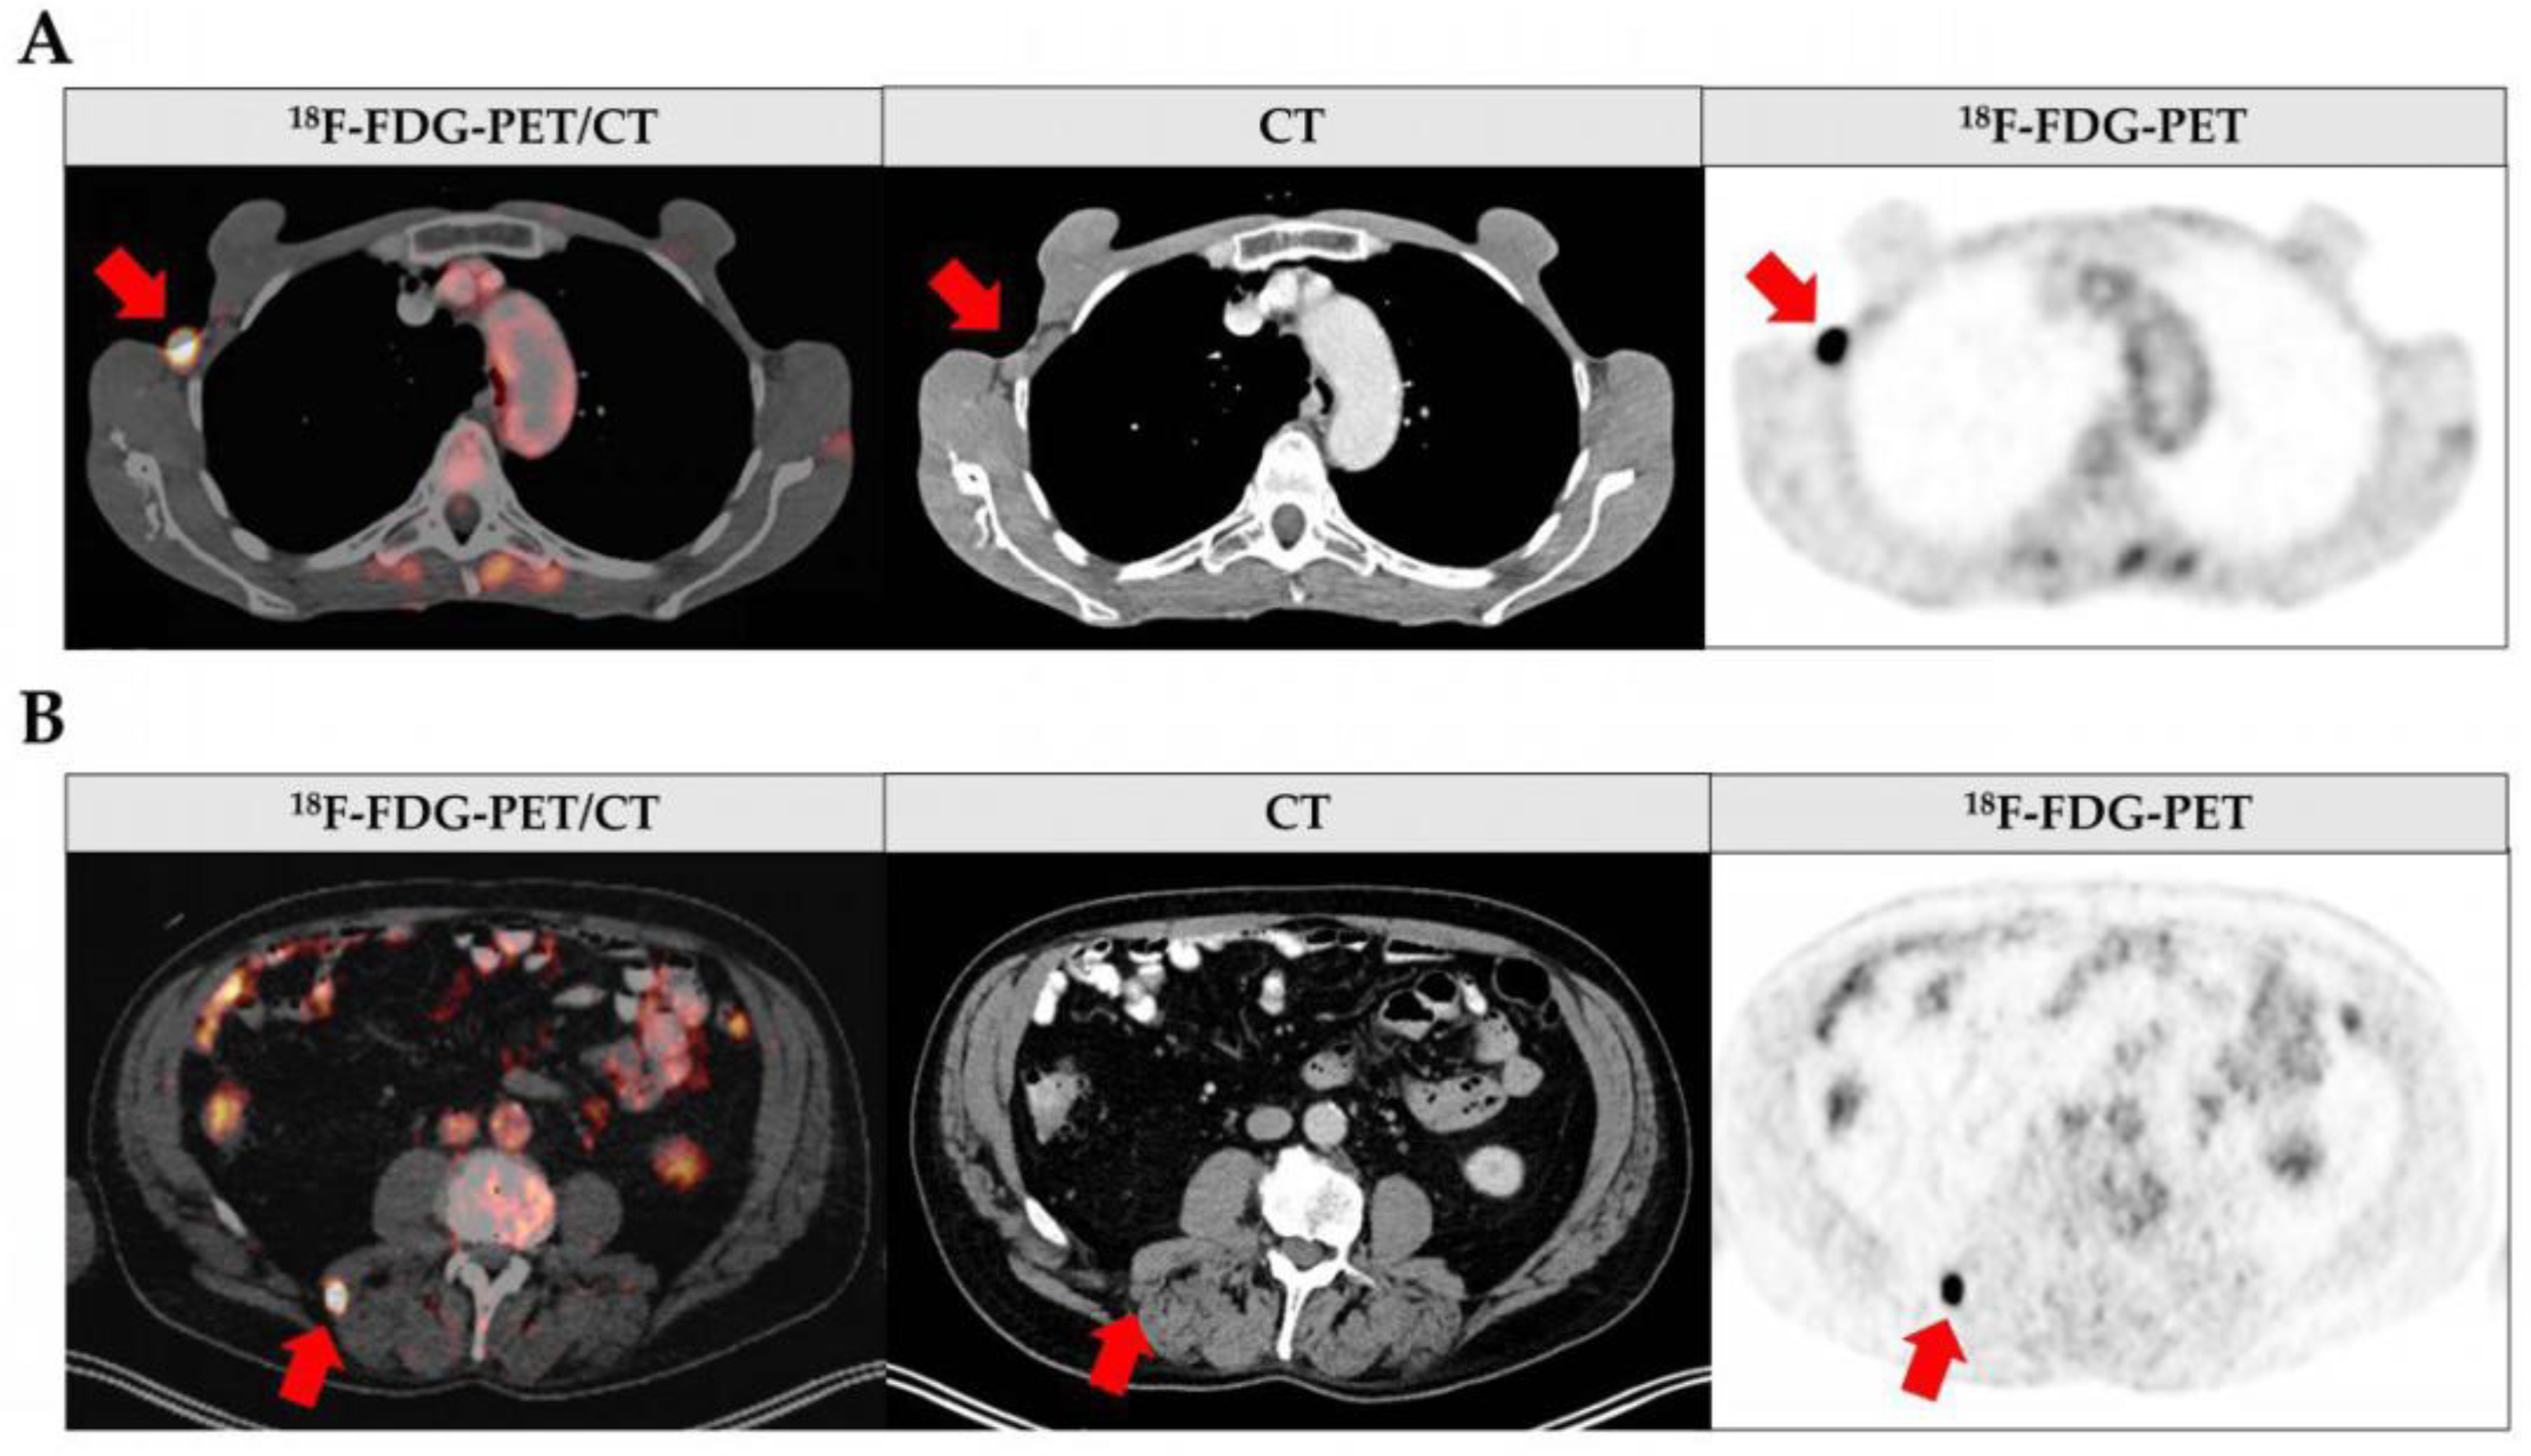

3.2. Results of Whole-Body 18F-FDG-PET/CT Imaging